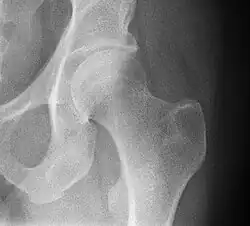

Radiograph of a healthy human hip joint

The hip joint or coxofemoral joint[5][6] is a ball and socket synovial joint formed by the articulation of the rounded head of the femur and the cup-like acetabulum of the pelvis.[7] The socket of the acetabulum is pointing downwards and anterolaterally. The socket is also turned such that the outer edge of its roof is more lateral than outer edge of the floor.[7] It forms the primary connection between the bones of the lower limb and the axial skeleton of the trunk and pelvis. Both joint surfaces are covered with a strong but lubricated layer called articular hyaline cartilage.

The cuplike acetabulum forms at the union of three pelvic bones — the ilium, pubis, and ischium.[8] The Y-shaped growth plate that separates them, the triradiate cartilage, is fused definitively at ages 14–16.[9] It is a special type of spheroidal or ball and socket joint where the roughly spherical femoral head is largely contained within the acetabulum and has an average radius of curvature of 2.5 cm.[10] The acetabulum grasps almost half the femoral ball, a grip deepened by a ring-shaped fibrocartilaginous lip, the acetabular labrum, which extends the joint beyond the equator.[8] The centre of the acetabulum (fovea) does not articulate to anything. Instead, it is lined with fat pad and attached to ligamentum teres. The acetabular labrum is horse-shoe shaped. Its inferior notch is bridged by transverse acetabular ligament.[7] The joint space between the femoral head and the superior acetabulum is normally between 2 and 7 mm.[11]